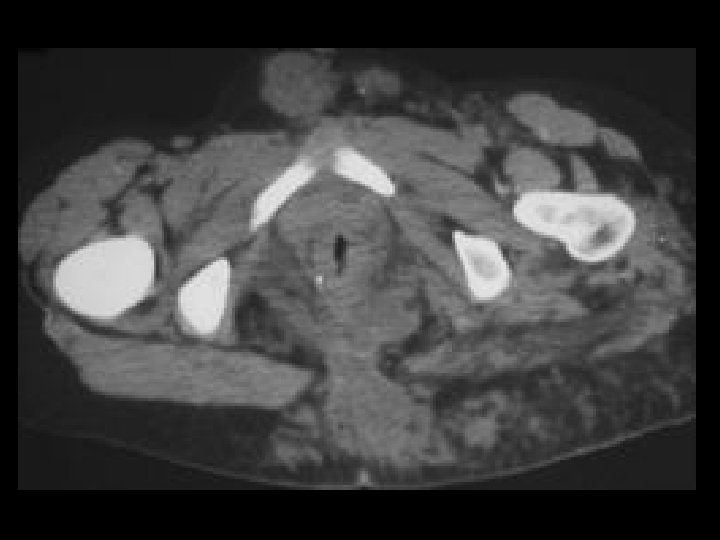

Neuroblastoma • Findings: – Large retroperitoneal mass encases the aorta and extends to the renal hilum – Peripheral enhancement and several foci of high density (? Ca 2+) • ddx: – Lymphoma – Metastatic LAN